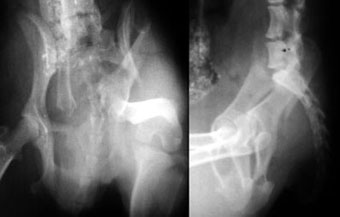

体重3kg、1歳齢の犬。

腸骨骨折と腹壁ヘルニアを起こしていました。

骨折部をプレート法により整復固定した後、腹壁ヘルニアの整復手術を実施しました。

写真上段: 手術前

骨盤の一部が割れて内側に変位しています。

写真下段: 手術後